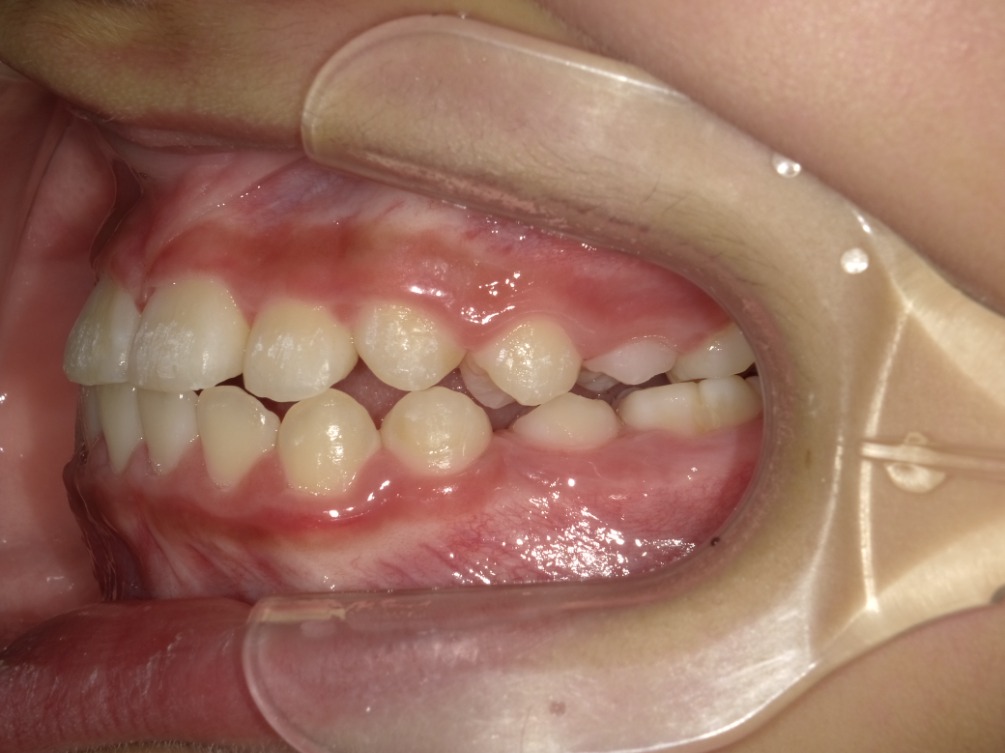

AFTER

右横

左横

| 治療内容 | インビザライン・ファースト |

| 治療詳細 | 叢生や交叉咬合を整えるために、歯の表面にアタッチメント(白い突起)をつけました。 |

| 主訴 | 歯のがたつき 一部分だけかみ合わせが反対 |